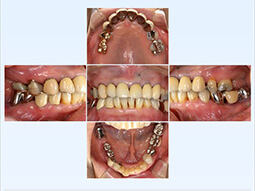

インプラント治療例その2(重度歯周病患者様、上顎に6本下顎に4本インプラント埋入、60歳代女性)

残念ながらここまで歯周病が広範囲かつ重度に進行してしまうと全て抜歯→総義歯が一般的な治療方針となりますが、患者様の強いご希望により必要最小限の本数を用いたインプラント治療によって、固定性補綴物による咀嚼回復が可能となりました。

暫間義歯を装着しCT撮影・診断の後インプラント埋入位置を決定、その位置へ正確に埋入するため作製されたサージカルガイドを用いて手術を行います。

術前

術後

術前レントゲン写真

術後レントゲン写真

| 治療内容 | インプラント治療(重度歯周病患者様、上顎に6本下顎に4本インプラント埋入) |

|---|---|

| 治療期間・回数 | 約6ケ月、5~6回 |

| 治療費用 | ¥4,870,000 |

| 治療のデメリット | 歯に比べ感染に弱いので、徹底した口腔衛生管理が必須 保険適用外のため、自費診療となる しっかり噛めるまで数ケ月かかる |